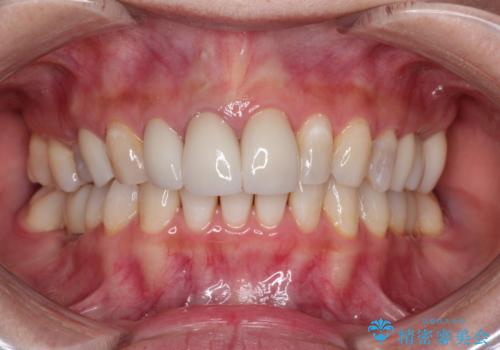

[ セラミック・インプラント全顎治療 ] 長年悩まされている歯の治療にケリをつけたい

![[ セラミック・インプラント全顎治療 ] 長年悩まされている歯の治療にケリをつけたいの症例 治療後](https://seimitsushinbi.jp/wp/wp-content/uploads/2022/01/f4f9ee9ff7018c558de74748d97a4667-500x350.jpg?v=1642042445)